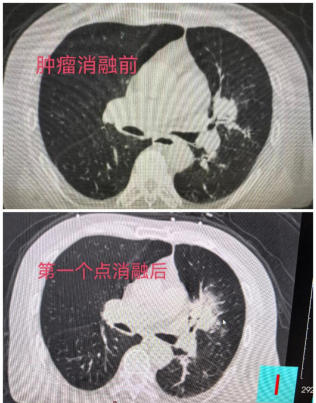

针对该患者的复杂病情,广元市第一人民医院呼吸与危重症医学科气道介入团队,联合国家呼吸医学中心、广医一院钟长镐教授团队,为其量身定制射频消融手术方案。术前,气道介入团队通过导航支气管镜科学规划消融路径,术中利用超声支气管镜精准明确消融位置,最终在CT引导下确认消融部位。在内镜中心全程配合、麻醉科保驾护航、各相关部门积极协调下,气道介入团队为其顺利实施经支气管肿瘤射频消融术。

术后,患者左肺上叶前段管腔通畅,未出现出血、气胸等并发症,复查胸部CT显示,肺部病灶已被全部覆盖。目前,患者身体状态良好,呼吸功能得到显著改善,已逐步恢复正常生活节奏。